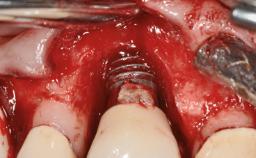

A 30-year-old female patient was referred to the Department of Periodontology of the University of Bern, Switzerland, by a dentist in private practice. Tooth 45 had been congenitally missing and had been replaced with a titanium implant three years prior to the first visit at the Department of Periodontology. The tissue level implant had a diameter of 4.1 mm, a length of 12 mm, and a sandblasted and acid-etched (SLA) surface (Straumann® Dental Implant System; Institut Straumann AG, Basel, Switzerland). The metal-ceramic crown on implant 45 had been cemented permanently. Implant 45 had been diagnosed with peri-implantitis by the referring dentist in the course of regular supportive care.